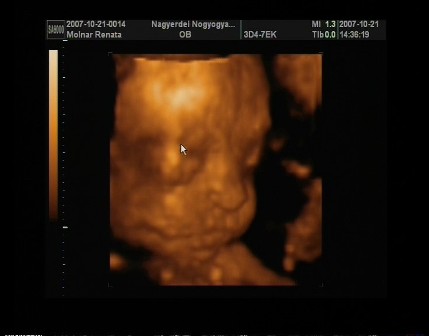

reni, na azt elhiszem hogy be vagytok már sózva az uh miatt!